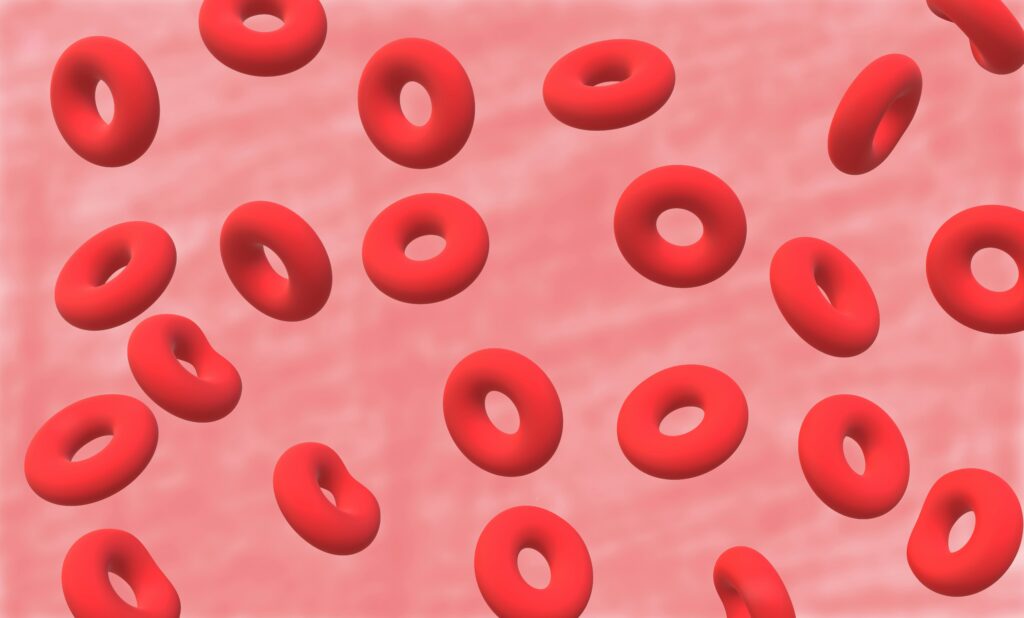

🫀 5. Your Blood Travels 12,000 Miles a Day

Every single day, your heart pumps about 2,000 gallons of blood through a network of vessels stretching more than 12,000 miles — half the distance around the Earth.

It’s the ultimate logistics network, delivering oxygen and nutrients to every corner of your body.

🩸 8. You Have Enough Iron in Your Blood to Forge a Small Nail

The iron in your blood gives it its red color — and there’s about 4 grams of it circulating through your veins.

If extracted, it could form a small metal nail.

That same iron helps transport oxygen and maintain cellular function.